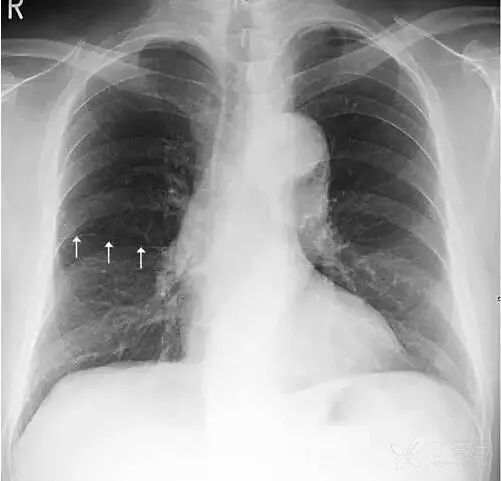

肩胛骨 如果投照时体位标准,上肢内旋充分,则肩胛骨应当位于肺野之外。否则肩胛骨将重叠于上肺野偏外的区域,呈与胸壁平行的条带状高密度影。此时可能会被误认为是肺内病变。仔细观察可见肩胛骨影从肺内向肺外延伸,即可与肺内病变区别。

上图摄片时双上肢未充分内旋,导致双侧肩胛骨大部分重叠于双肺中上肺野中外带,导致相应肺野条带状密度增高。白色箭头标示右侧肩胛骨内侧缘,向肺外延续。左侧肩胛骨情况类似。